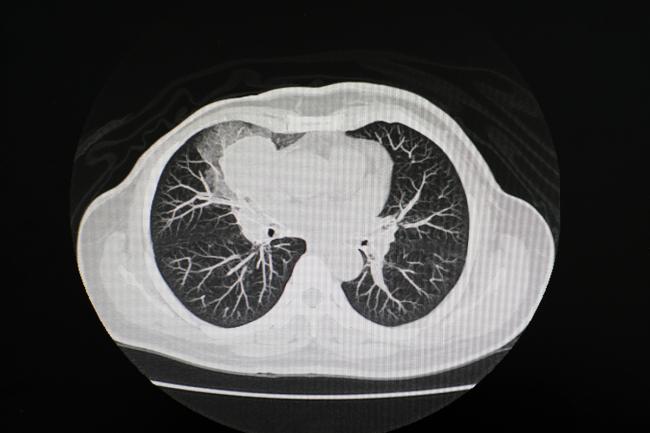

The researchers ramped up the difficulty further by challenging Merlin to interpret CT scans of the chest, a body part completely absent from its CT study material. Merlin’s unique ability to identify generalizable features of disease allowed it to perform as well as or better than models trained exclusively on chest scans.